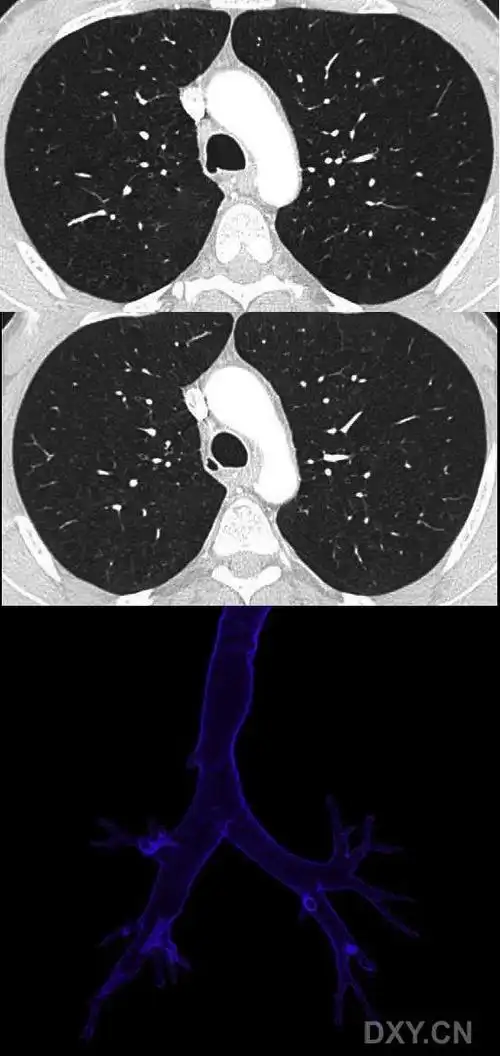

图123‐3 气道三维重建

下面是三维重建的图像:在5毫米层厚的平扫上只有这一个层面可见,非常